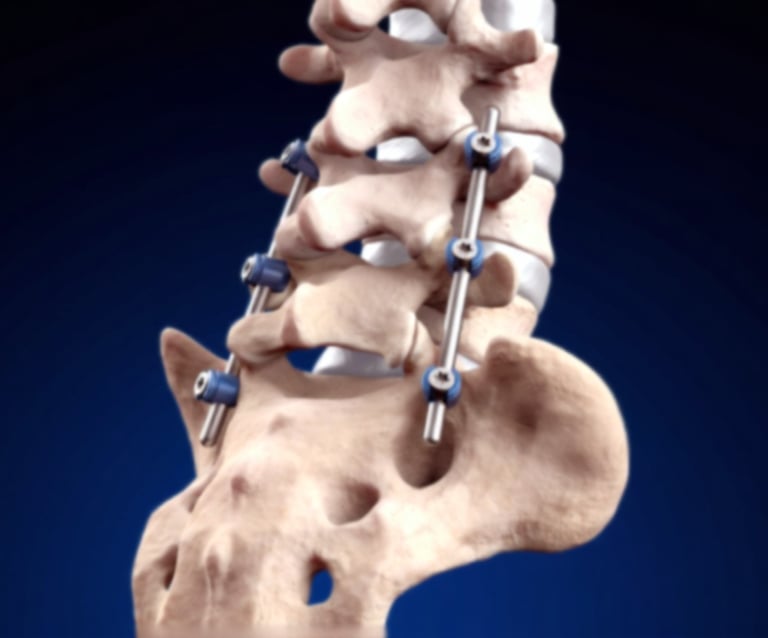

Spinal Fusion Surgery

A surgical procedure that permanently connects two or more vertebrae to eliminate motion between them. Used to treat instability, severe degenerative disc disease, spinal deformities, or spondylolisthesis by creating a solid bridge of bone—stabilizing the spine, relieving pain, and preventing further progression of the condition.